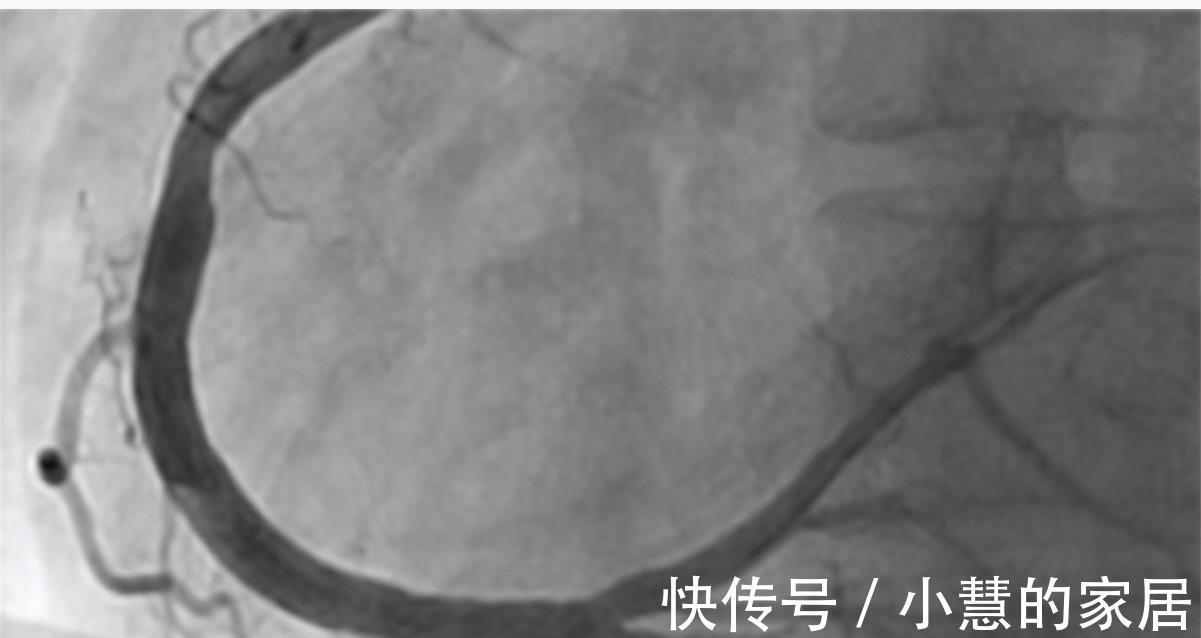

高大爷向医生说明了自己8年的冠心病史和一直没有服用药物的状态,医生害怕高大爷的病情进一步加重,于是做了简单的查体后就安排了高大爷住院进行心脏冠脉造影的检查。检查结果出来后,医生十分奇怪高大爷的情况。

患者体温36.5℃、血压130/90、身高168cm、体重68kg。心电图提示心脏存在明显早搏现象。心脏造影显示主动脉堵塞百分之二十三,排除冠心病。